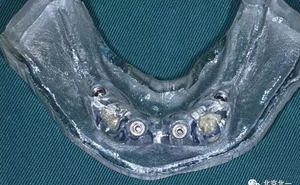

圖三:終末導(dǎo)板

圖十六:術(shù)后三個(gè)月永久修復(fù)取模,夾板固定。

圖十七:拍X片確認(rèn)無誤差